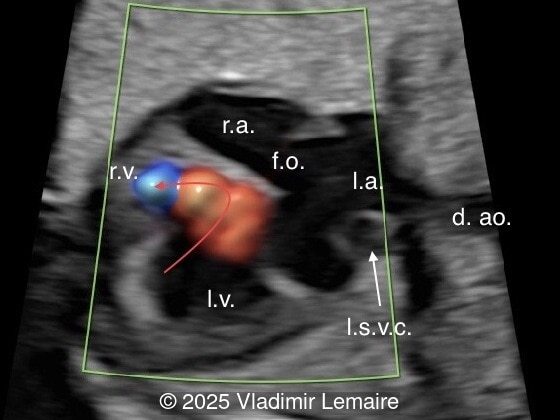

We present a case of isolated tricuspid atresia type 1 with persistent left superior vena cava. No other extracardiac anomalies were found. Our diagnosis was confirmed after birth.

In the images below, the abbreviations are as follows: RA: right atrium; RV: right ventricle; LV: left ventricle; MV: mitral valve; LA: left atrium; FO: foramen ovale; SVC: superior vena cava; LSVC: left superior vena cava; PV: pulmonary veins; PA: pulmonary artery; MPA: main pulmonary artery; RPA: right pulmonary artery; AO: aorta; dAO: descending aorta; aAO: ascending aorta; DA: ductus arteriosus; T: trachea; * marks the ventricular septal defect.

Right ventricular outflow tract view.

Image 5 Right ventricular outflow tract view.

Color Doppler confirms the diagnosis on grayscale ultrasound, as it demonstrates the lack of blood flow across the tricuspid valve and a patent mitral valve. Due to increased blood flow across the mitral valve, aliasing is typically noted on color Doppler. Mitral valve regurgitation has been associated with a poor outcome. The right ventricular cavity is filled in late diastole from the left ventricle, through the ventricular septal defect. Left-to-right shunting across the ventricular septal defect can be seen on color Doppler. Color Doppler is helpful in the evaluation of flow across the great arteries. Flow across the pulmonary artery is generally antegrade. Pulmonary stenosis should be suspected when the vessel is diminutive in size rather than the demonstration of turbulent flow on color Doppler, which is typically absent in these cases.

Associated cardiac findings include a large interatrial communication such as a patent foramen ovale or an atrial septal defect, transposition of the great arteries, and various degrees of ventricular outflow obstruction. Ventricular outflow obstruction can vary from patent pulmonary artery to stenosis and atresia, and from patent aortic arch to aortic stenosis, coarctation, or interruption of the aortic arch. Other associated cardiac lesions include persistent left superior vena cava as presented in this case, right aortic arch, pulmonary venous abnormalities, and juxtaposition of the atrial appendages. Extracardiac anomalies can be found in tricuspid atresia and there is a rare association with chromosomal aberration such as microdeletion 22q11. Fetal karyotyping should be offered.